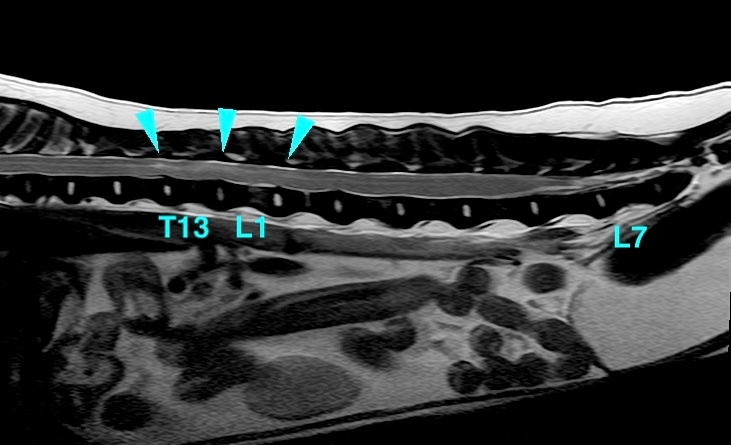

<症例情報> ウェルシュ・コーギー10歳 去勢雄 【主訴】数ヶ月前から後ろ足の進行性麻痺を認めた→MRI検査を実施 …